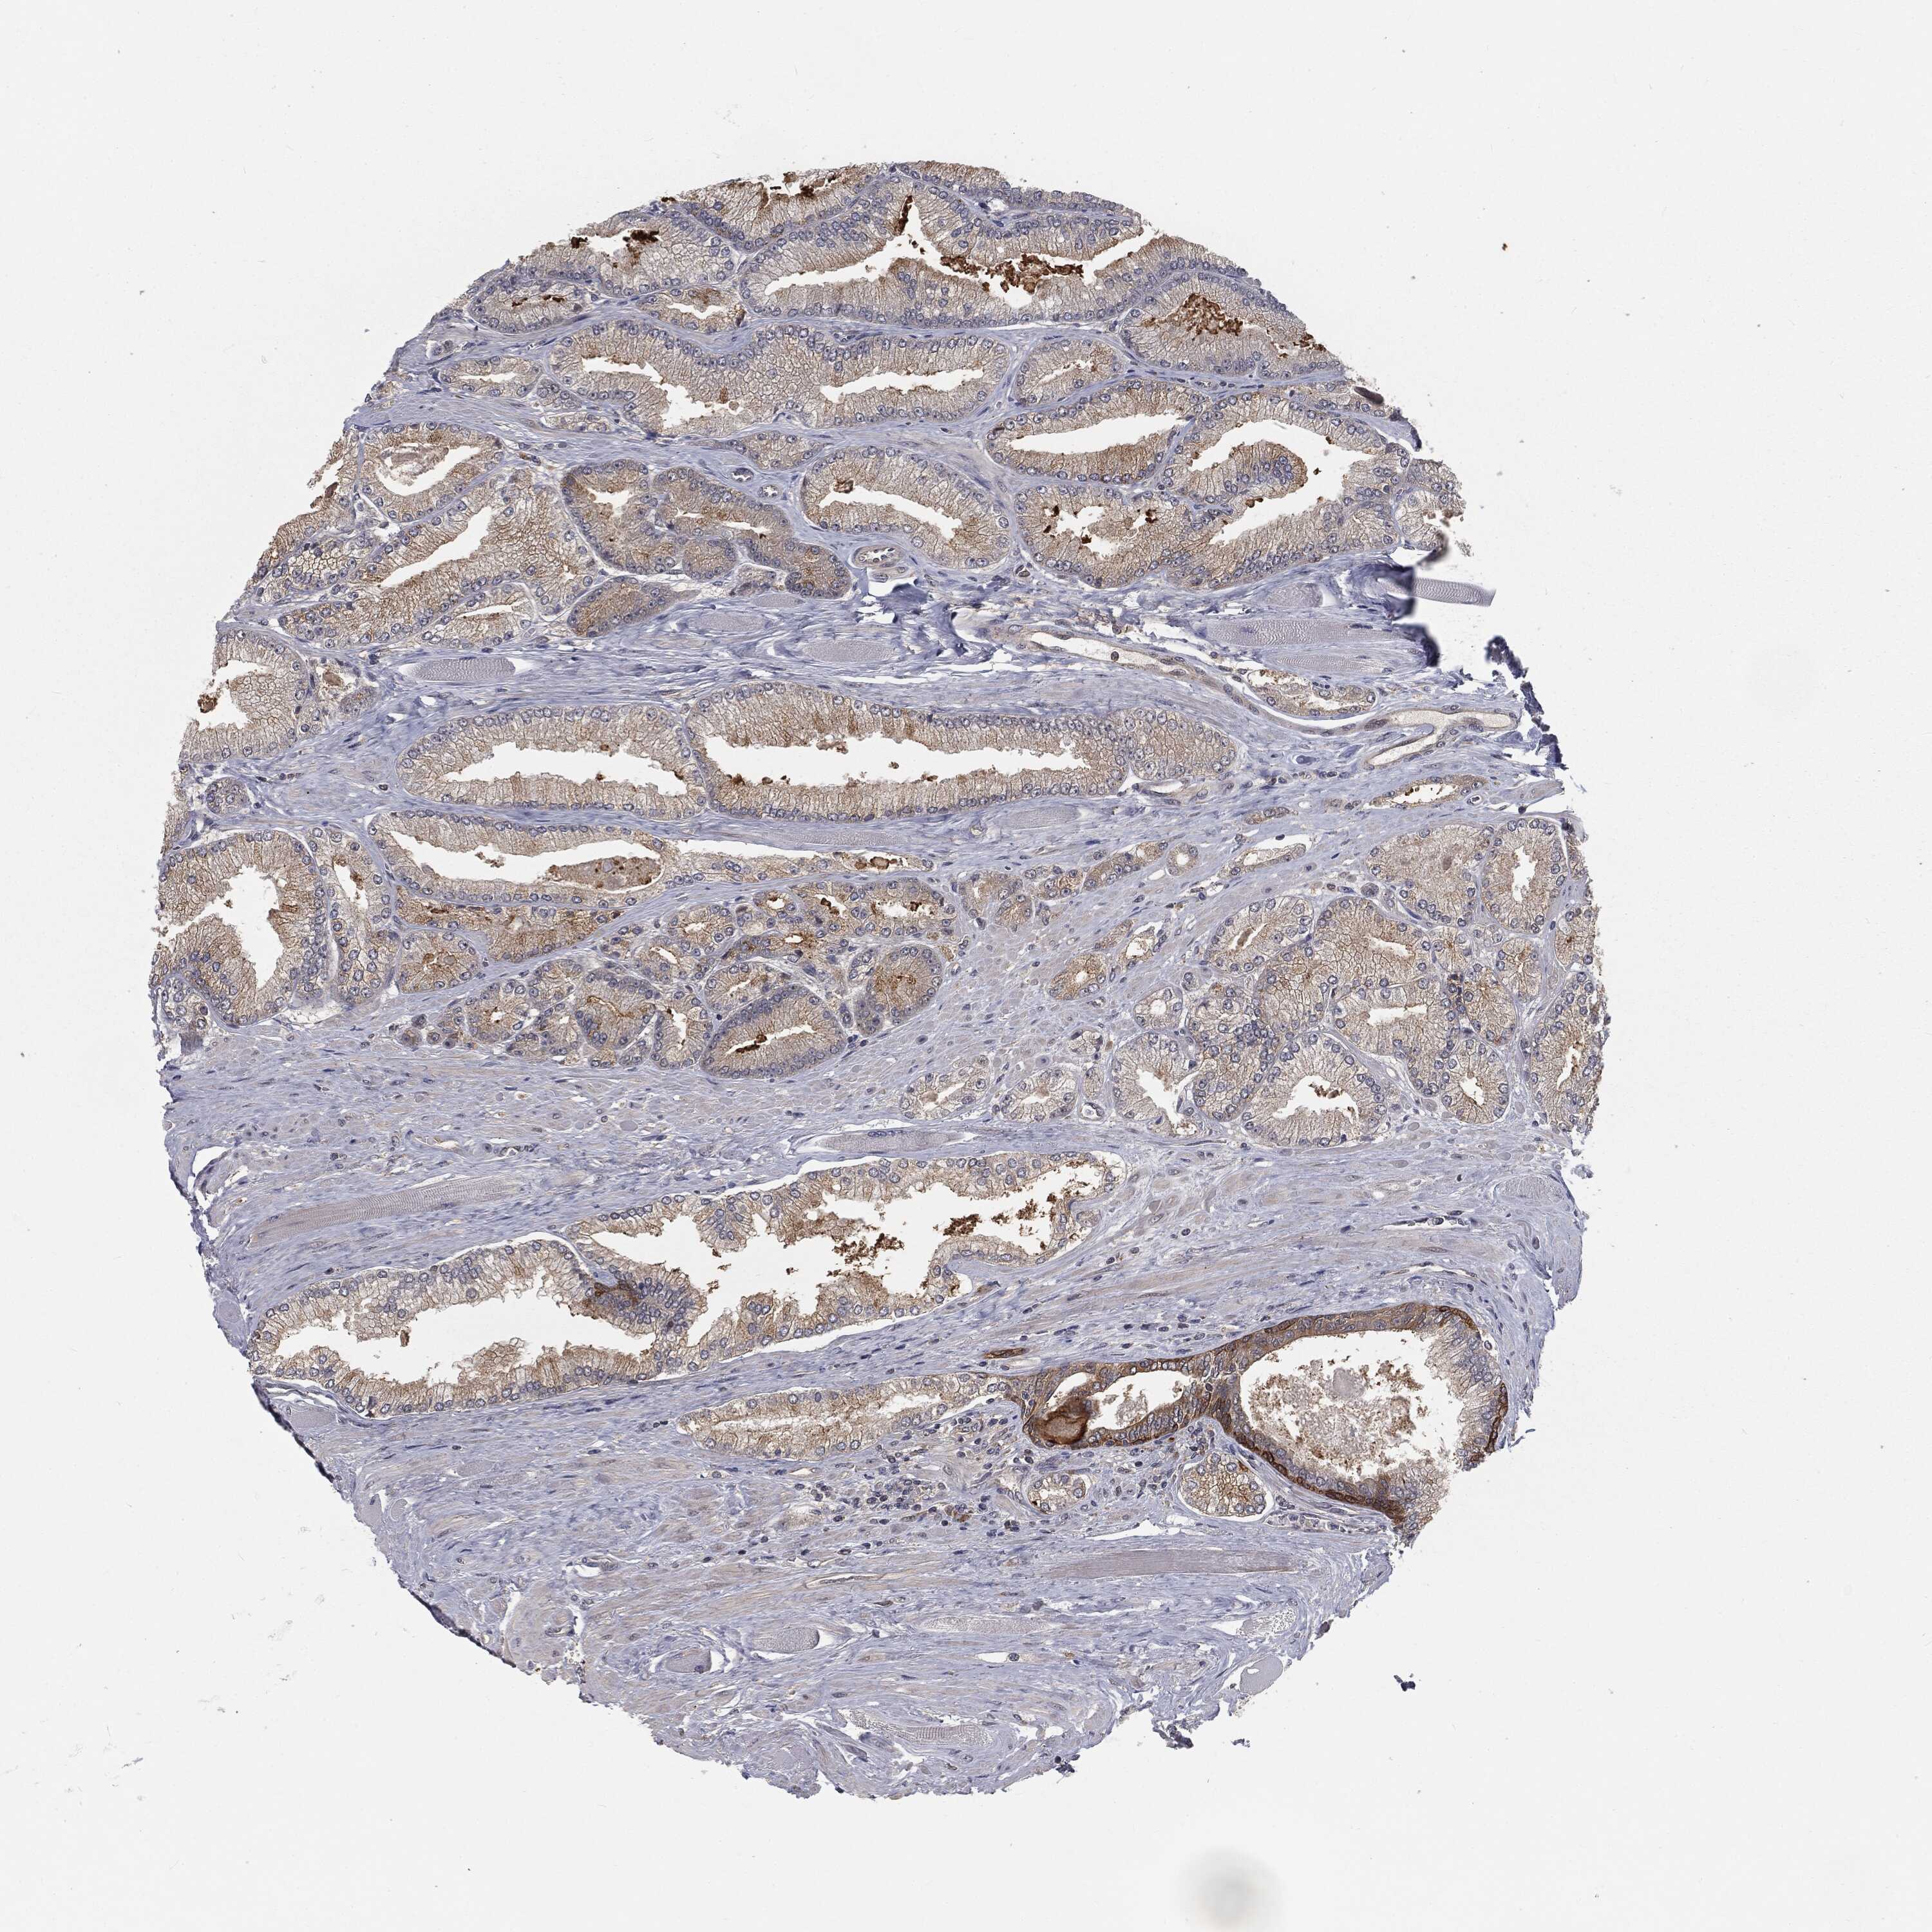

PROSTATE CANCER - Protein expressioni

A mouse-over function shows sample information and annotation data. Click on an image to view it in a full screen mode. Samples can be filtered based on level of antibody staining by selecting one or several of the following categories: high, medium, low and not detected. The assay and annotation is described here.

Antibody stainingi

Antibody staining in the annotated cell types in the current human tissue is reported as not detected, low, medium, or high, based on conventional immunohistochemistry profiling in selected tissues. This score is based on the combination of the staining intensity and fraction of stained cells.

Each image is clickable and will lead to virtual microscopy that enables deeper exploration of all samples and also displays staining intensity scores, fraction scores and subcellular localization as well as patient and tissue information for each sample.

Antibody HPA032114

Antibody HPA057352

Antibody CAB034296

Staining

High

Medium

Low

Not detected

Intensity

Strong

Moderate

Weak

Negative

Quantity

>75%

75%-25%

<25%

None

Location

Nuclear

Cytoplasmic/membranous

Cytoplasmic/membranous,nuclear

Adenocarcinoma, NOS

Adenocarcinoma, High grade

Adenocarcinoma, Low grade